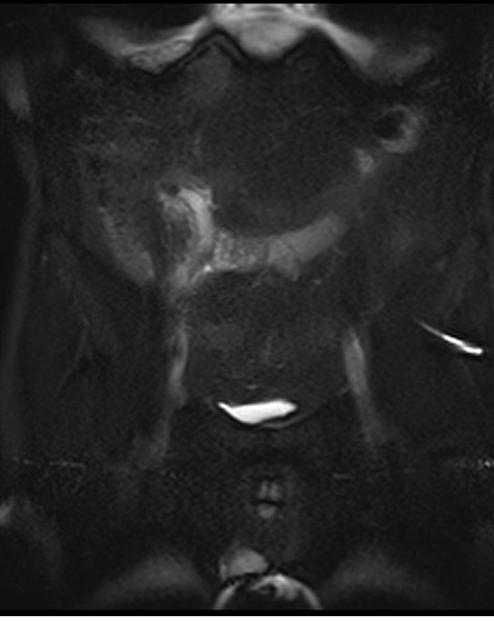

- MRT nəticələri KT ilə eynidir, hamilə qadınlarda diaqnostik çətinlik olarsa istifadə edilir.

Şəkil 2. Appendisitin diaqnostikası